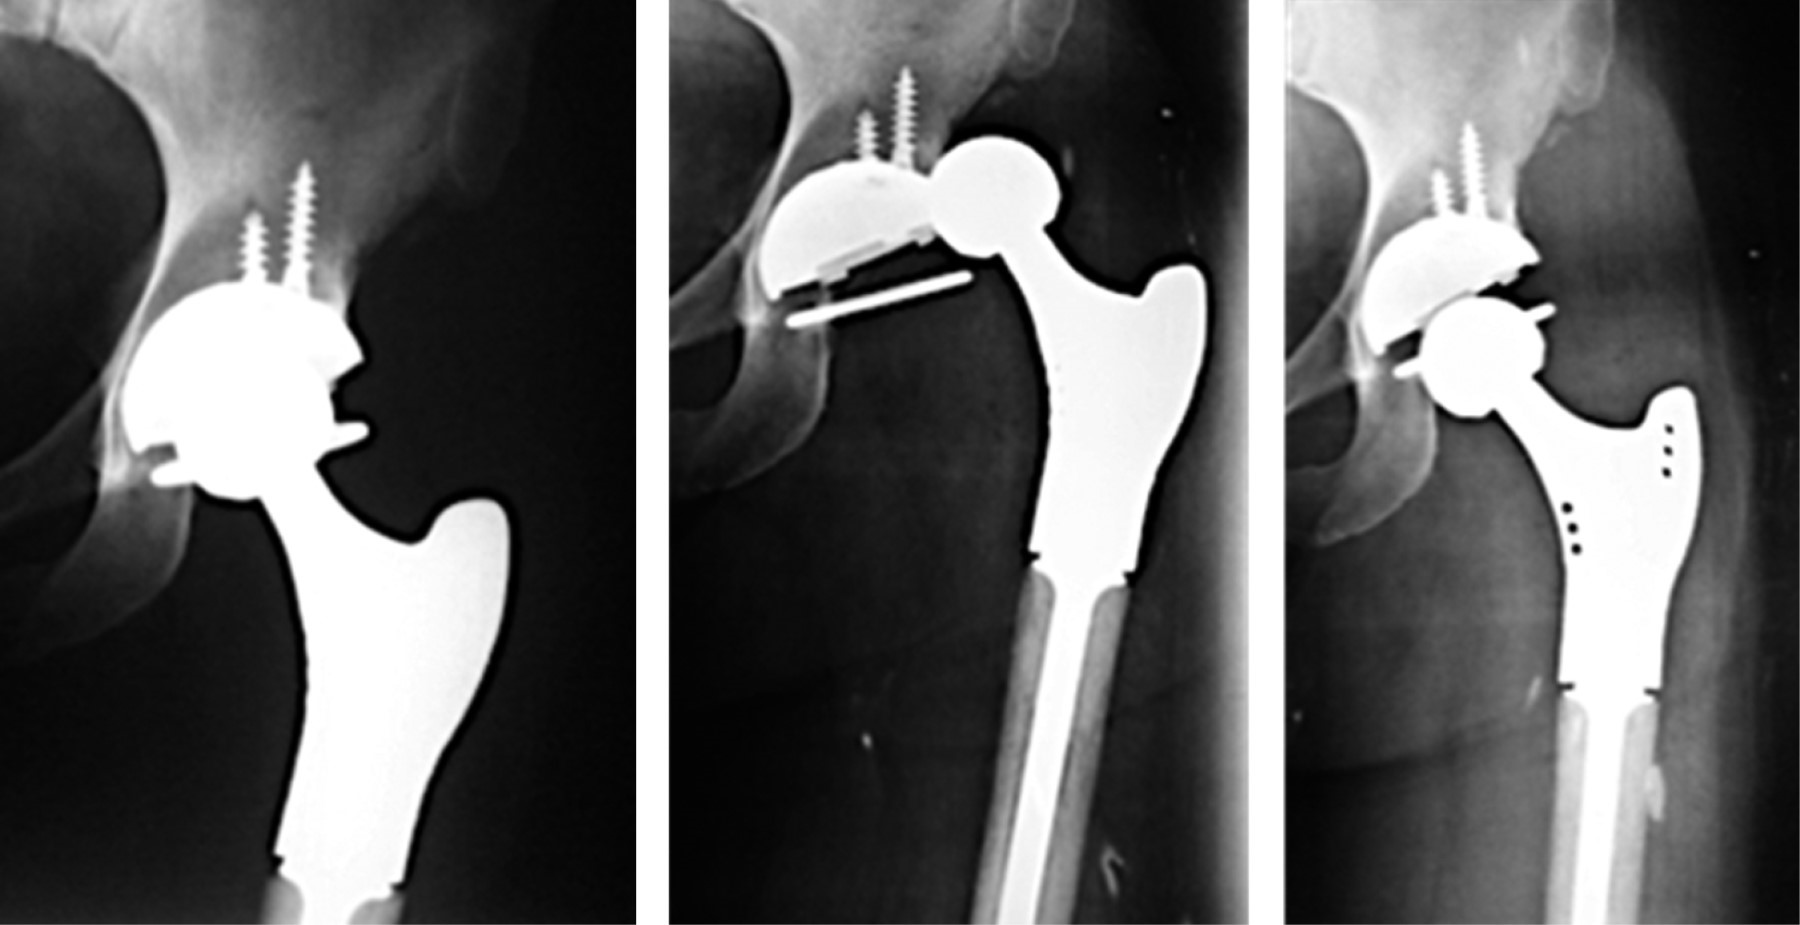

Acetábulos encarcelados o "constreñidos". Este recurso se ha empleado sobre todo en casos de revisión por luxación recidivante de la prótesis y ha sido muy solicitado para lo mismo con resultados razonablemente buenos. En el caso de estos acetábulos hay en el mercado diversos modelos (Figura 3).

Todos ellos tienen como principio la utilización de un anillo "retentivo" colocado casi al final de un inserto –que es más largo que uno de media esfera convencional– y pueden ser metálicos o de polietileno. Evidentemente la extensión distal obligatoria del inserto, limita los arcos de movilidad. Hay tres problemas relevantes de estos dispositivos: a) riesgo aumentado de colisión entre el borde del inserto contra el cuello del vástago, b) en muchos de ellos no es posible hacer reducciones cerradas (Figura 4) y c) su tasa de revisión es alta.18

Doble movilidad. El concepto de DM tiene casi cinco décadas de historia y fue desarrollado en Francia por Gilles Bousquet y André Rambert.7 Desde su aparición en 1974 han existido múltiples innovaciones a la idea original, de tal manera que actualmente hay un verdadero boom de copas de DM; muchas de ellas cuentan con versiones cementadas y no cementadas (Figura 5).

Los diseños de los modelos contemporáneos actuales de DM son principalmente de tres tipos: a) subhemiesféricos, b) modulares con un inserto metálico con extensión distal cilíndrica y c) anatómicos (Figura 6). Algunos ya se fabrican con impresión 3D. Ya que hay variedad en los diseños y modelos, cada uno de ellos con atributos propios, es necesario mantenerlos en constante vigilancia y estar alertas a sus resultados a largo plazo para adoptar las conductas pertinentes en cuanto a su correcta indicación y utilización. A continuación, revisaremos algunos aspectos de estos implantes.